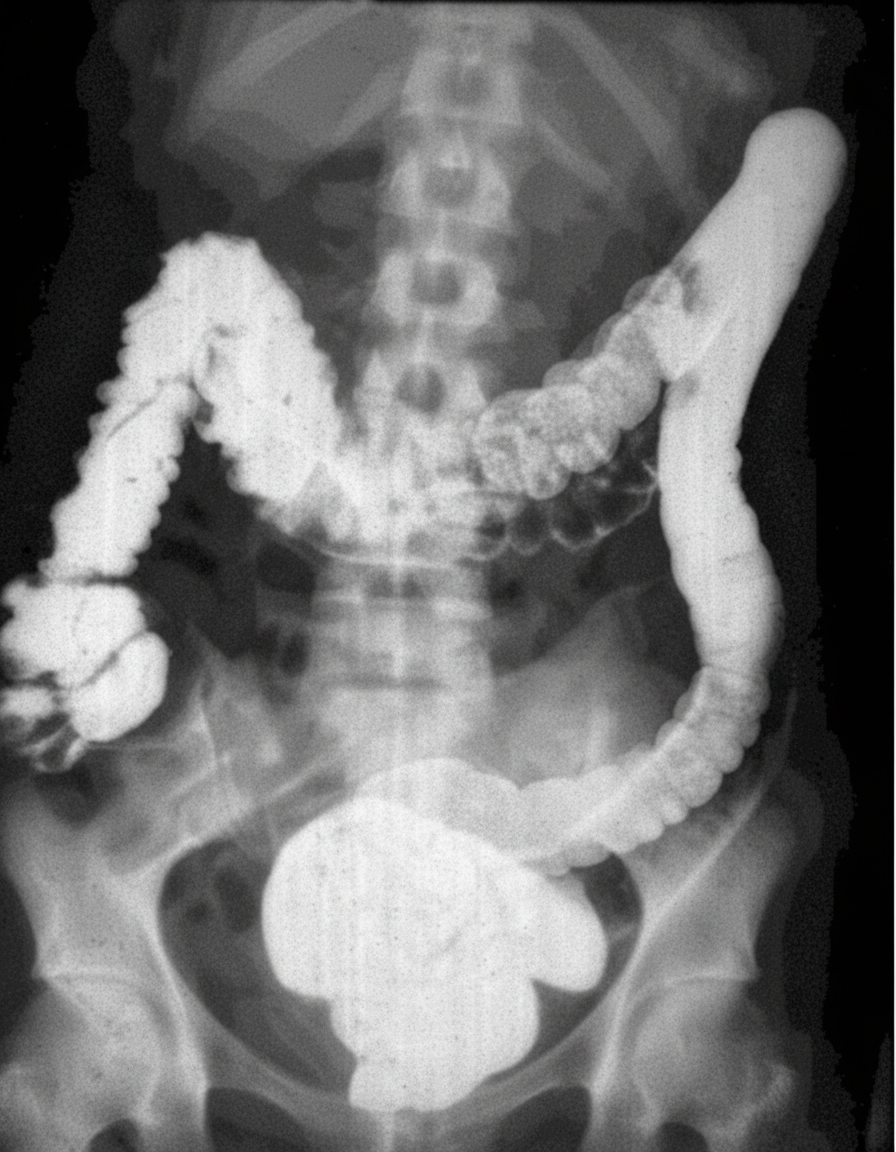

All of the following statements regarding this picture are true except:

Explanation: ***This condition is associated with APC gene of chromosome 4*** - The APC gene is located on **chromosome 5q21-q22**, not chromosome 4. - Mutations in the **APC gene** are responsible for **Familial Adenomatous Polyposis (FAP)**. *More than 100 colonic adenomas are diagnostic of this condition* - The presence of **more than 100 colonic adenomas** (often hundreds to thousands) is the diagnostic criterion for **Familial Adenomatous Polyposis (FAP)**. - The image provided shows a colon segment densely packed with numerous polyps, consistent with FAP. *Associated with ampullary carcinoma* - Patients with FAP have an increased risk of developing **extracolonic manifestations**, including **duodenal adenomas** and **ampullary carcinomas**. - This association is a significant concern in FAP management due to the aggressive nature of these tumors. *This condition is associated with benign mesodermal tumors such as desmoid tumors and osteomas* - **Gardner syndrome**, a phenotypic variant of FAP, is characterized by colonic polyposis along with **extra-intestinal manifestations**, including **osteomas** (especially of the skull and mandible) and **desmoid tumors**. - Desmoid tumors are locally aggressive fibroblast proliferations, often occurring in the abdominal wall or mesentery in FAP patients. *Prophylactic colectomy is recommended due to nearly 100% risk of colorectal cancer* - Patients with FAP have a **nearly 100% lifetime risk** of developing colorectal cancer if untreated. - **Prophylactic colectomy** (total or subtotal) is the standard of care, typically performed in late adolescence or early adulthood. - Surgical options include **total proctocolectomy with ileal pouch-anal anastomosis (IPAA)** or **subtotal colectomy with ileorectal anastomosis**.

Explanation: **They are a result of tractional force** - Diverticula as visualized in the image are **pulsion diverticula**, formed due to increased intraluminal pressure pushing the mucosa through weak points in the muscular wall. - **Traction diverticula** are true diverticula involving all layers of the bowel wall, and are typically caused by inflammation or scarring pulling the bowel wall outwards (e.g., in tuberculosis or histoplasmosis near the esophagus), which is not the mechanism for colonic diverticula shown. *False diverticulum* - The image depicts multiple outpouchings, which are characteristic of **false diverticula** (pseudodiverticula). - These diverticula involve only the **mucosa and submucosa** herniating through the muscular layer, lacking a complete muscular coat. *Most common site for this defect is sigmoid colon* - **Colonic diverticula** are most commonly found in the **sigmoid colon** due to its smaller diameter and higher intraluminal pressure, which predisposes it to outpouching. - The characteristic appearance of multiple small outpouchings in the image suggests colonic diverticulosis, consistent with the sigmoid colon being the primary location. *High fiber diet will reduce the incidence of this defect* - A **low-fiber diet** is considered a major risk factor for developing diverticulosis, as it leads to harder stools and increased intraluminal pressure. - Conversely, a **high-fiber diet** promotes softer stools, reduces intracolonic pressure, and is therefore believed to **reduce the incidence** and progression of diverticular disease. *Asymptomatic in majority of cases* - **Diverticulosis** (the presence of diverticula) is asymptomatic in approximately **70-80% of cases**. - Most patients are diagnosed incidentally during colonoscopy or imaging performed for other reasons. - Only a minority develop complications such as diverticulitis, bleeding, or perforation.